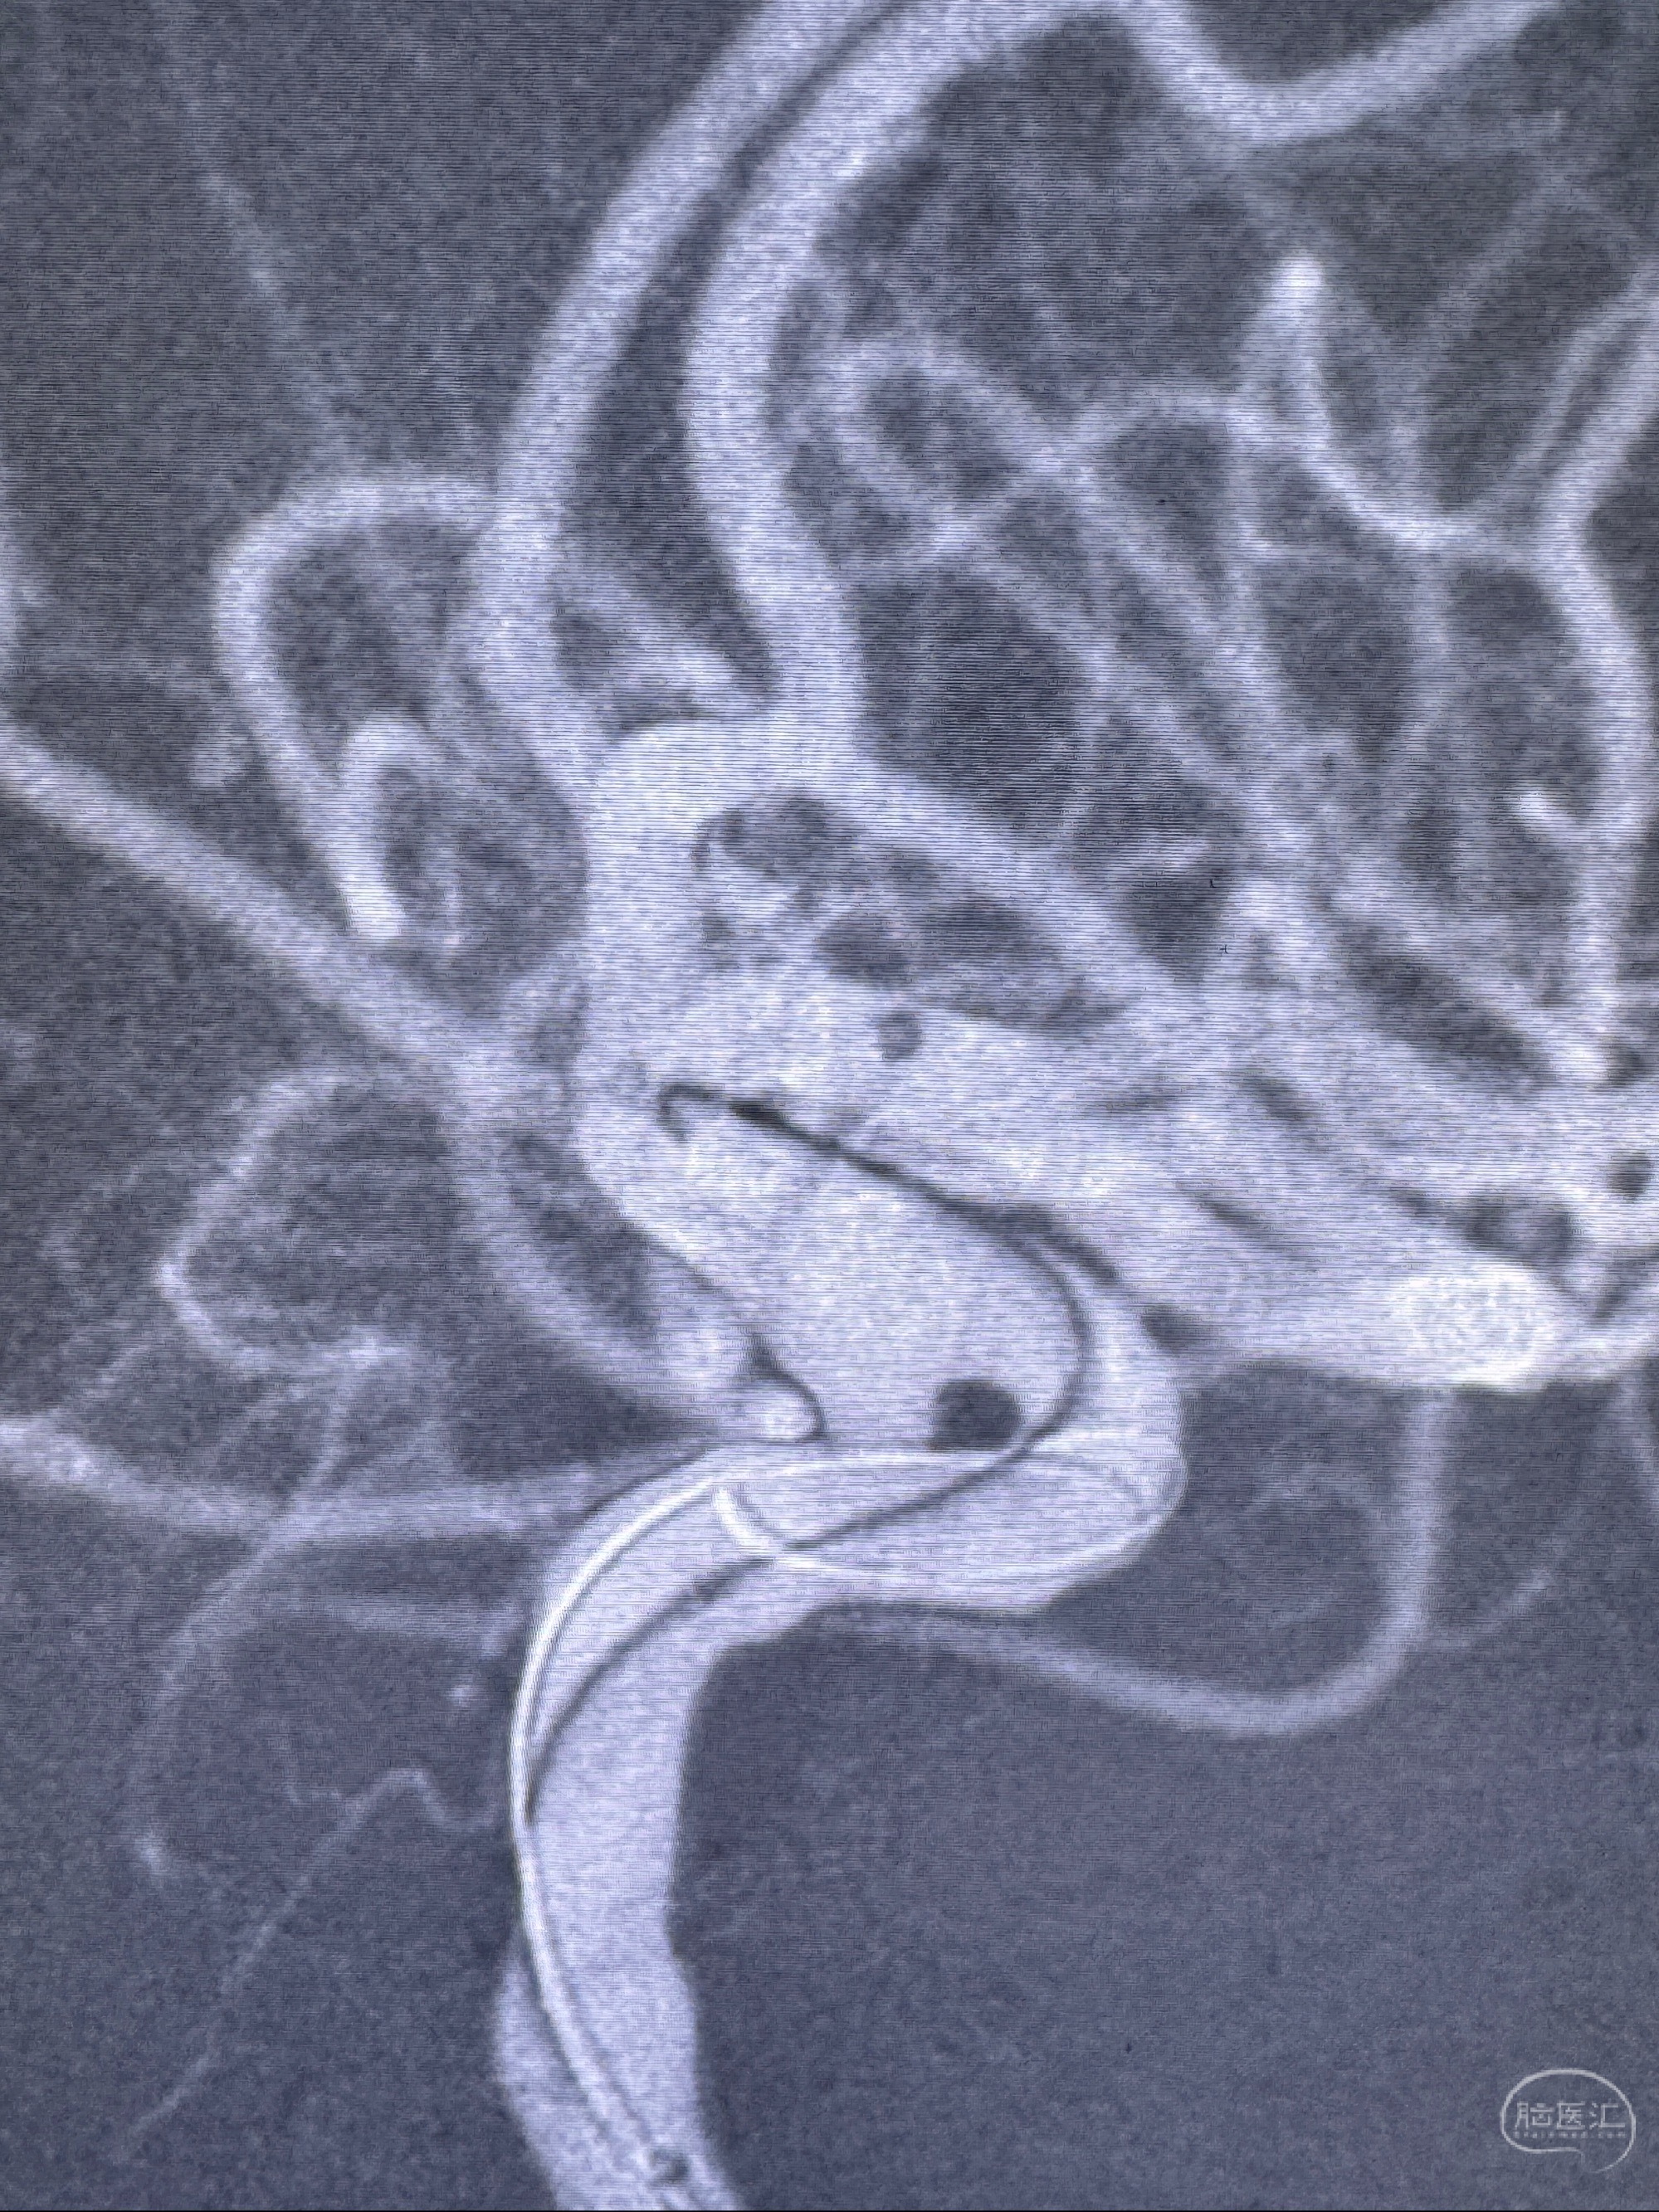

2023-11-13DSA:左侧颈内动脉眼动脉后壁动脉瘤

2023-11-29全麻下行NeuroformEZ4.5-20mm支架辅助栓塞

麻醉苏醒佳,遵嘱动作